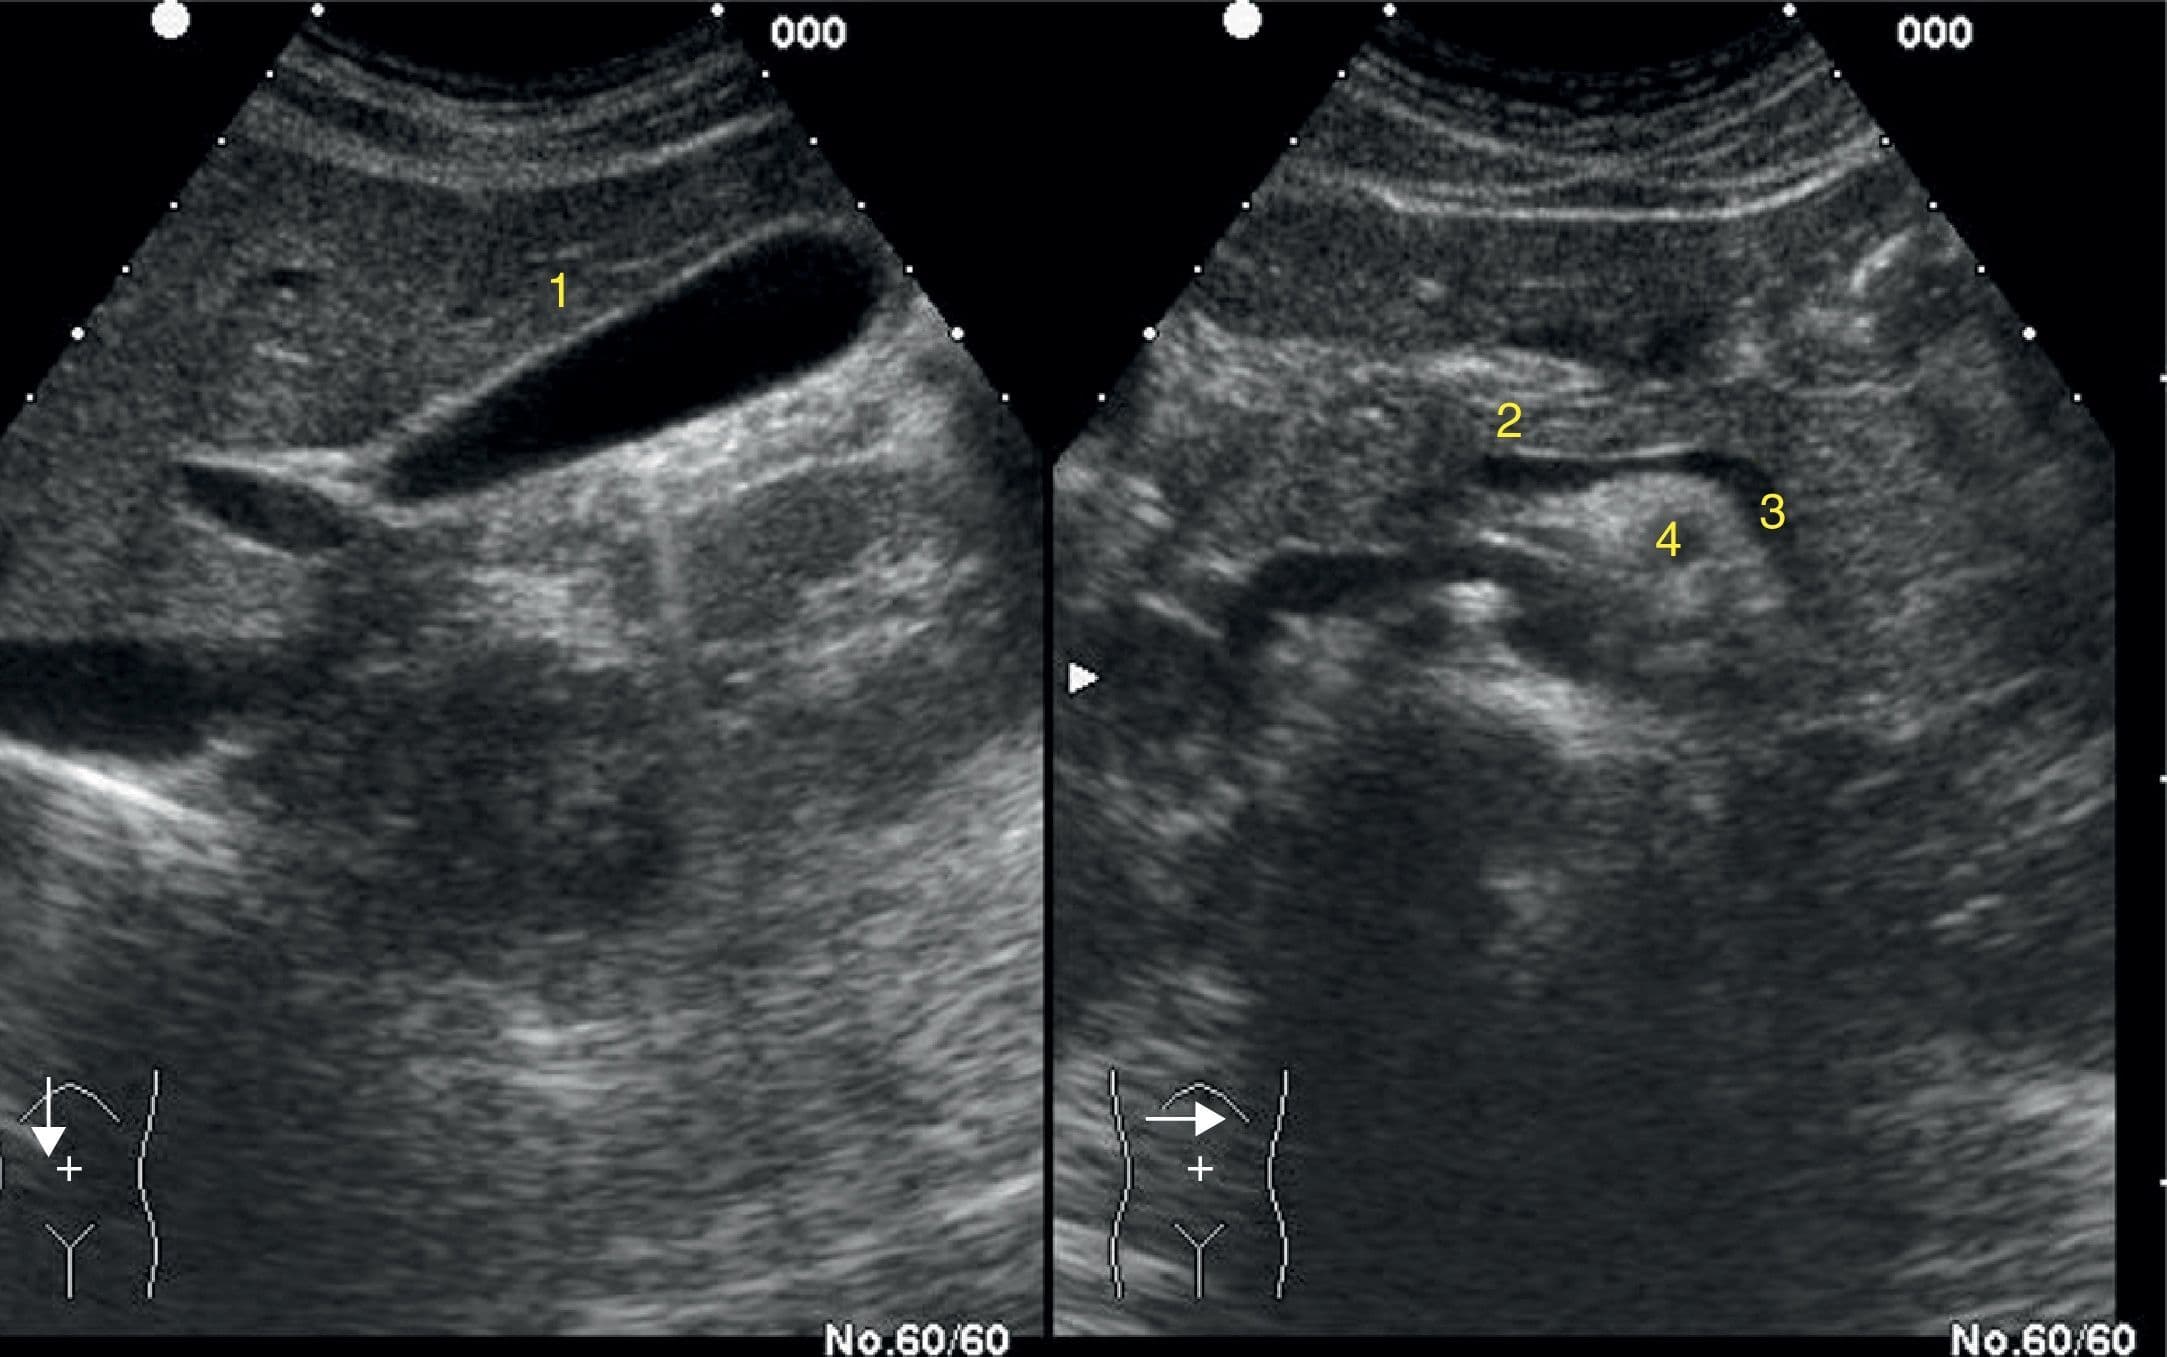

Dr: Vengo a Consulta porque me duele este lado desde hace varios meses, y mi médico de Cabecera me dijo que necesitaría una ecografía de abdomen...

Doctor; llevo varios meses que me da un dolor aquí en el lado derecho, abajito de la costillla, se me va a la espalda, tengo naúseas y vomito, me du...